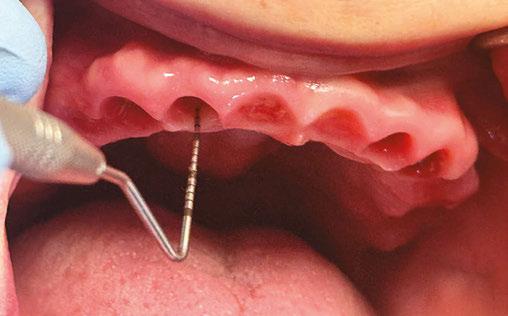

Probing tissue 3-months after 3 on 6 surgery with about 5 mm of tissue above the TRI implants

Clinical examination revealed probing depths of 5–6 mm around implant Nos. 4 and 5, with thread exposure at implant No. 5 above the gingival margin. Radiographic examination revealed bone loss around implant Nos. 4 and 5, leading to a diagnosis of peri-implantitis (Figure 3A). Although no significant biofilm accumulation was visible to the naked eye (Figure 3B), evaluation using QLF clearly detected biofilm that was not observable under conventional visual inspection (Figure 3C). Considering the patient’s osteoporosis and the fact that only 4 months had passed since her last denosumab (Prolia®) injection, flap surgery was not performed. Instead, curettage was selected as the treatment approach.

For biofilm removal, cleansing was performed using an ultrasonic scaler (Megagen, Seoul, South Korea), a curette, and a microbrush. After mechanical debridement, QLF imaging was conducted again to compare pre- and post-treatment findings. While no biofilm was visible to the naked eye (Figure 3D), QLF revealed residual biofilm on the implant threads (Figure 3E). Additional debridement was carried out, followed by another round of clinical and QLF imaging for confirmation (Figures 3F-3G). This process enabled a more thorough evaluation of biofilm removal and served as a visual aid for patient education on oral hygiene. Targeted brushing instruction (TBI) was also provided.